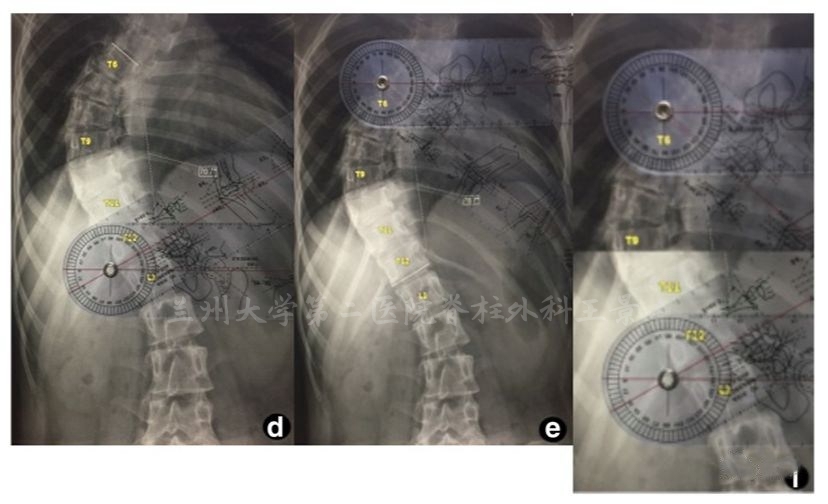

如法炮制,拍照测量脊柱侧弯Cobb角

为方便演示,照片标注上、下端椎终板连线

旋转照片使终板连线和网格线重叠

读出上、下端椎的倾角绝对值

相加后就是Cobb角

端椎倾角法快速测量Cobb角